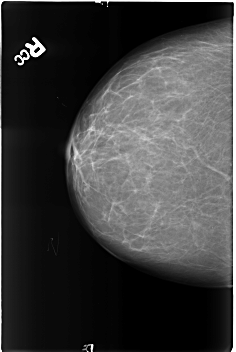

B_3165_1.RIGHT_CC

RIGHT_CC LINES 4568 PIXELS_PER_LINE 3064 BITS_PER_PIXEL 12 RESOLUTION 50 NON_OVERLAY